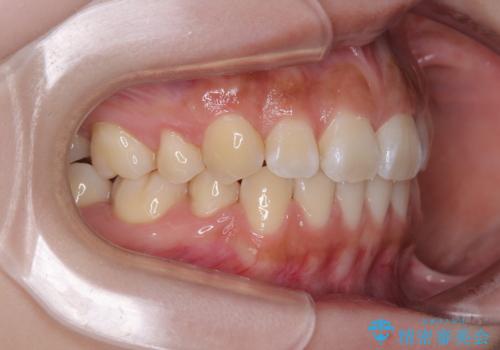

口元の印象が劇的に解消され、気にしていたガミースマイルも図らずも改善することができました。

上下前歯が嘴のように前方に突出しており、唇が閉じにくい状態であったため、上下左右の第一小臼歯4本を抜歯して、口元の突出感を改善することとしました。